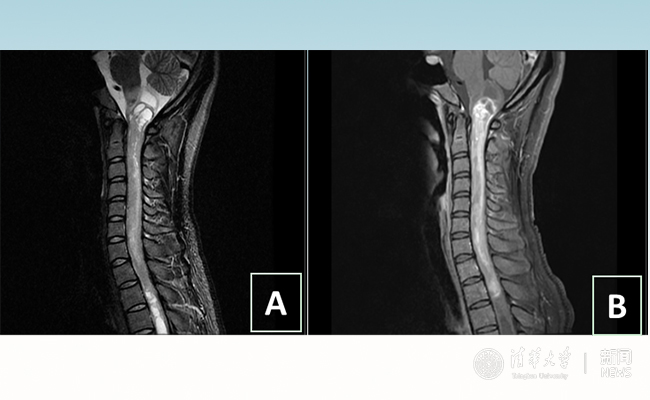

2018.01拯救“90后”女孩 清华长庚神经外科切除20多公分髓内肿瘤

“愿得韶华刹那,开得满树芳华。”27岁的患者小甜(化名)在华体会娱乐平台附属北京清华长庚医院成功进行了手术,神经外科主任王贵怀为其切除了自延髓至胸髓的长达20余公分的脊髓内肿瘤。1月9日,小甜顺利出院,再续芳华!